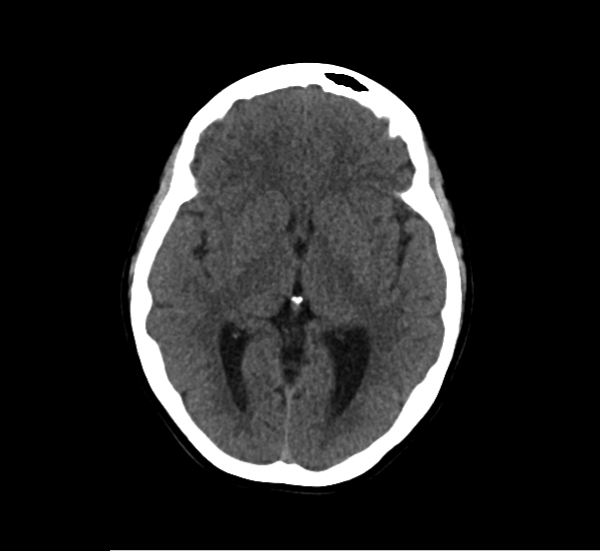

CT Brain Anatomy